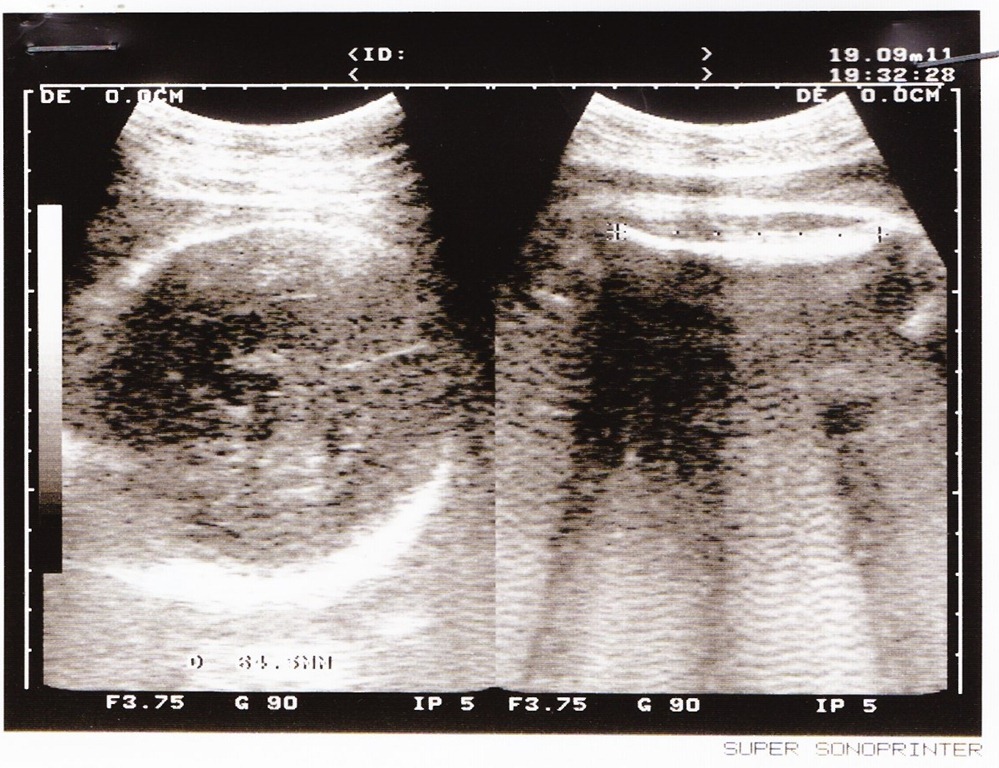

100/9/19 35周大,2450克

媽媽說:這時之後的超音波照,因為美樂蒂長大了,都是局部的畫面,有些我也看不出來是拍那個部位……

![]()

100/10/3 37周3天,2750g

這兩周長了300g,一下衝到2750克了!媽媽說我的腳超有力氣的,總是一腳踢左邊,頂到最末端,另一腳再踢肚子中間。